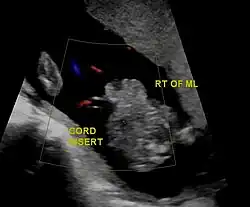

| Diagnostic method | Ultrasound during pregnancy, based on symptom at birth[2] |

In the developed world, around 90% of cases are identified during normal ultrasound screens, usually in the second trimester.[17]